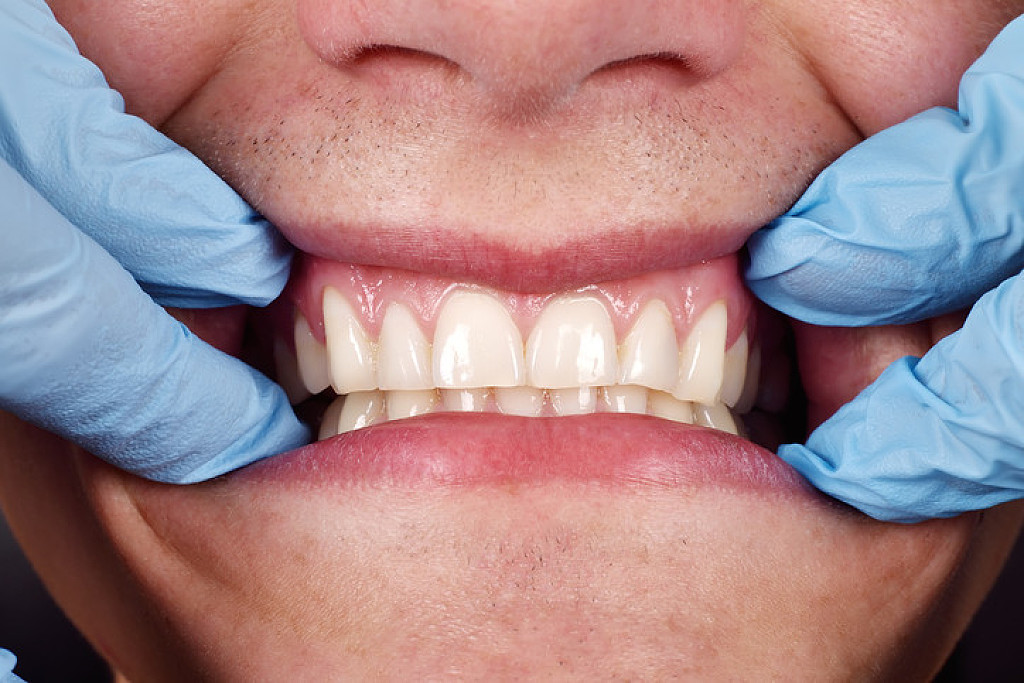

In the end, the overgrown gums may need to be surgically removed. The AAOM notes that good oral hygiene, especially the effective removal of plaque between the teeth, can alleviate the condition. In the case of drug-induced overgrowths, if patients are not able to discontinue the medication, surgical removal may be the only effective treatment. This can be done with a scalpel or laser.

However, if the root cause is not adjusted, the enlargement will return, and surgery may have to be performed numerous times. Pressure devices that look like night guards are sometimes used to try and limit the rate of rebound of the tissues. Also, your dentist may have you return every three months to clean the areas to limit the effects of inflammation on the soft tissues.